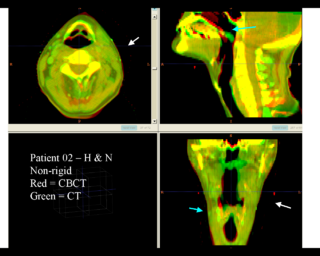

Below are some examples of anatomic change in head & neck and thorax.

Rigid registration

Deformable registration